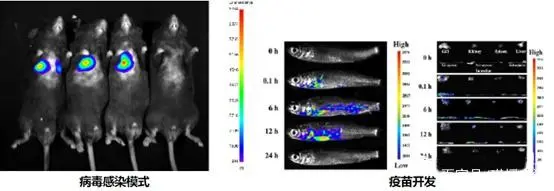

利用一套非常灵敏的光学检测仪器,让研究人员能够直接监控活体生物体内的细胞活动和基因行为。通过这个系统,可以观测活体动物体内肿瘤的生长及转移、感染性疾病发展过程、特定基因的表达等生物学过程。